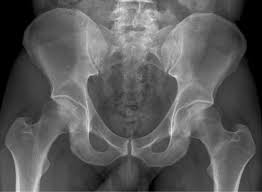

If an x-ray or MRI at the sports clinic confirms that youre experiencing a stress fracture in the hip the doctor will likely instruct you to rest. There are different operations which are. This depends on the fracture site and whether it is a simple crack or a displaced fracture.

Stress fractures under the femoral neck are less likely to be displaced and therefore they are usually treated by nonsurgical procedures. Treatment for hip fracture usually involves a combination of surgery rehabilitation and medication. Stop any moderate activity and repetitive stressful exercises running squatting cycling.

Medications for Stress Fractures You can take over-the-counter medications to manage pain. Initial treatment of a hip stress fracture may include X-rays a magnetic resonance imaging MRI scan or a bone scan to further evaluate your condition.

Stress Fracture Of The Hip